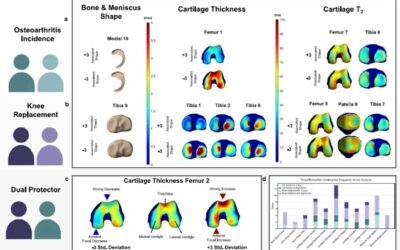

qMRI Biomarkers for OA & Knee Replacement

This study forms the basis of a digital twin system of the knee joint, using...